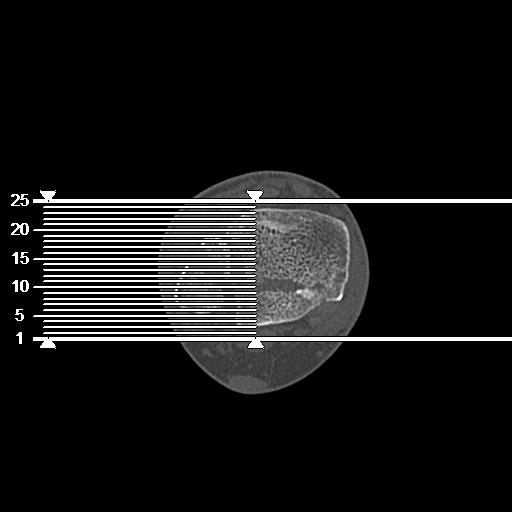

100612 11/25 1/20 右膝 2R 84歳女性 右TKA